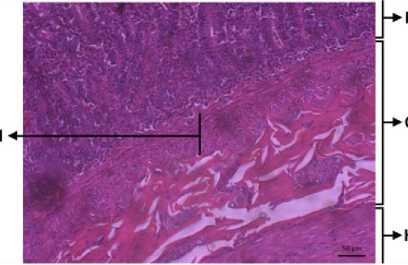

Picture 1. Tunica Mucousa (HE) (200X) A: Villi, B: Lamina Propria, C: Epitel, D: Goblet cell

Picture 2. Tunica Mucousa (HE) (200X) E: Crypt Lieberkuhn

Picture 3. Histologi Duodenum (HE) (200X) F: Tunica Mucousa, G: Tunica Submucousa, H: Tunica Muscularis I: Lamina Muscularis

Picture 4. Tunica Submucousa (HE) (200X), J: Kelenjar Sekresi

Hasil penelitian menunjukkan bahwa struktur histologi duodenum anjing kintamani betina tersusun oleh empat lapisan, tunika mukosa, submukosa, muskularis dan serosa. Tunika mukosa merupakan bagian paling dalam pada lapisan duodenum. Banyak kelenjar yang mengeluarkan lendir ke dalam lumen untuk melumasi dinding usus melindungi dari gesekan cyme. Tunika mukosa terdiri dari tiga lapisan, lamina mukosa, propria, dan muskularis seperti yang dilaporkan oleh William et al. (2012) dan Althnaian et al. (2013).

Epitel yang ditemukan pada duodenum anjing kintamani yaitu epitel kolumner simplek. Lamina mukosa terdiri dari epitel kolumner simplek. Didalam tunika mukosa terdapat villi pada duodenum. Villi berfungsi untuk memperluas permukaan penyerapan. Sel-sel yang ditemukan di epitel adalah sel kolumner "sel absorptif". Sel goblet terpencar di antara sel kolumnar villi dan kriptus. Lamina propria menempati sebagian besar tunika mukosa. Lamina propria diperluas melalui inti villi, terdiri dari jaringan ikat longgar yang membentuk kerangka tunika mukosa, pembuluh darah, pembuluh getah bening dan otot polos (Althnaian et al., 2013). Lamina propria mengandung serabut elastis, leukosit, dan otot polos yang bersifat soliter berjalan dari muskularis mukosa sampai ke ujung villus (Suwiti, 2012).

Sel-sel yang ditemukan dalam lamina propria adalah sel goblet, crypt lieberkuhn, sama halnya yang dilaporkan oleh William et al. (2012). Sel goblet atau biasanya disebut sel mangkok letaknya tersebar diantara sel penyerap dan melekat pada juxta-luminal junctional complex, daerah kutub basalnya menyempit dan mengndung inti dan sitoplasma bersifat basofil (Suwiti, 2012). Lamina muskularis adalah lapisan otot polos yang memisahkan tunika mukosa dengan tunika submukosa (Althnaian et al., 2013). Pada lapisan tunika submukosa ditemukan kelenjar brunner dan unit sekresi. Pada lapisan tunika muskularis terdapat 2 lapisan muskularis longitudinal dan sirkular, kemudian terdapat pembuluh darah dan saraf, lapisan tunika muskularis yang berisi jaringan otot polos. Otot akan berkontraksi jika adanya chyme dan mendorongnya, hal ini diperkuat dari laporan William et al. (2012). Serosa adalah lapisan terluar dari duodenum yang berfungsi sebagai kulit luar usus. Membran serosa yang terbuat dari epitel skuamosa sederhana memberikan permukaan licin dan mulus untuk mencegah friksi antara duodenum dan organ di sekitarnya. Serosa juga mengeluarkan cairan serosa untuk

lebih mengurangi gesekan dan menjaga duodenum. Pada lapisan tunika serosa terdiri dari jaringan ikat longgar yang berlanjut dengan mesenterium.